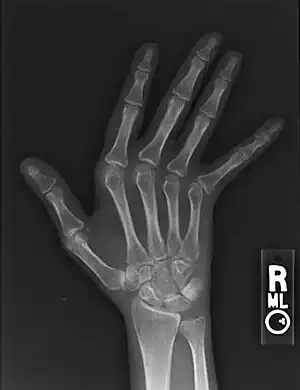

| Jaccoud arthropathy seen on a hand x-ray. As opposed to arthropathy due to rheumatoid arthritis, there are no erosions. | |

Plain hand radiographs typically show marked ulnar subluxation and deviation at the metacarpophalangeal joints. Absence of erosions is a notable feature, although occasionally "hook" erosions may be observed, which are similar to those seen in SLE and ankylosing spondylitis. Evidence of muscle (soft tissue) atrophy also may be present.